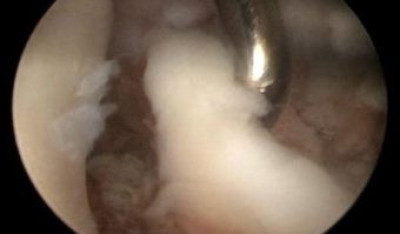

Palpación con un instrumento la parte anterior de articulación del codo